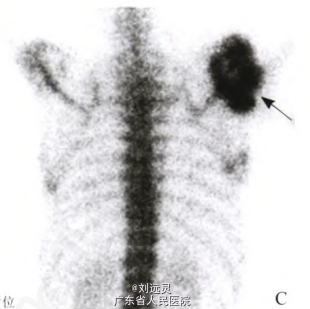

男,43岁,以右肩病变入院。10年前依据症状及颈部MRJ诊断为C1~C6水平脊髓空洞症,后根据病史、X线及穿刺活检在外院诊断为Charcot关节病(Charcot’s anhrosis,CA)。

体格检查:右肩关节肿胀、活动无受限,无红肿,皮温不高,压痛不明显,触及大小约12 cm×10 cm×10 cm囊性肿块,质软,有波动感。右上肢肌力正常,右肩关节及右侧胸部触觉及痛觉降低,上肢肌肉和大鱼际肌较对侧萎缩。

诊断:脊髓空洞症合、Charcot关节病 处理:减少活动和支架保护是多用的有效方法。